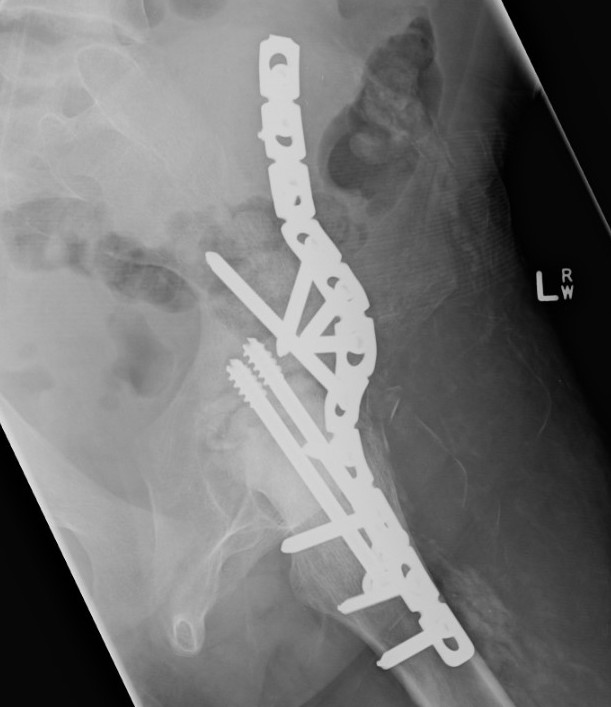

Extra-articular Intra-articular Combined intra-articular + anterior plate

Hip Fusion Cobra Plate Hip Fusion AP Hip Fusion 1Hip fusion 2

Fixation

- 150° DHS / 6.5 mm cannulated screws

- through joint into thick supra-acetabular area of ilium

- supplement with additional screws as necessary

Anterior plate onto lateral aspect of iliac crest